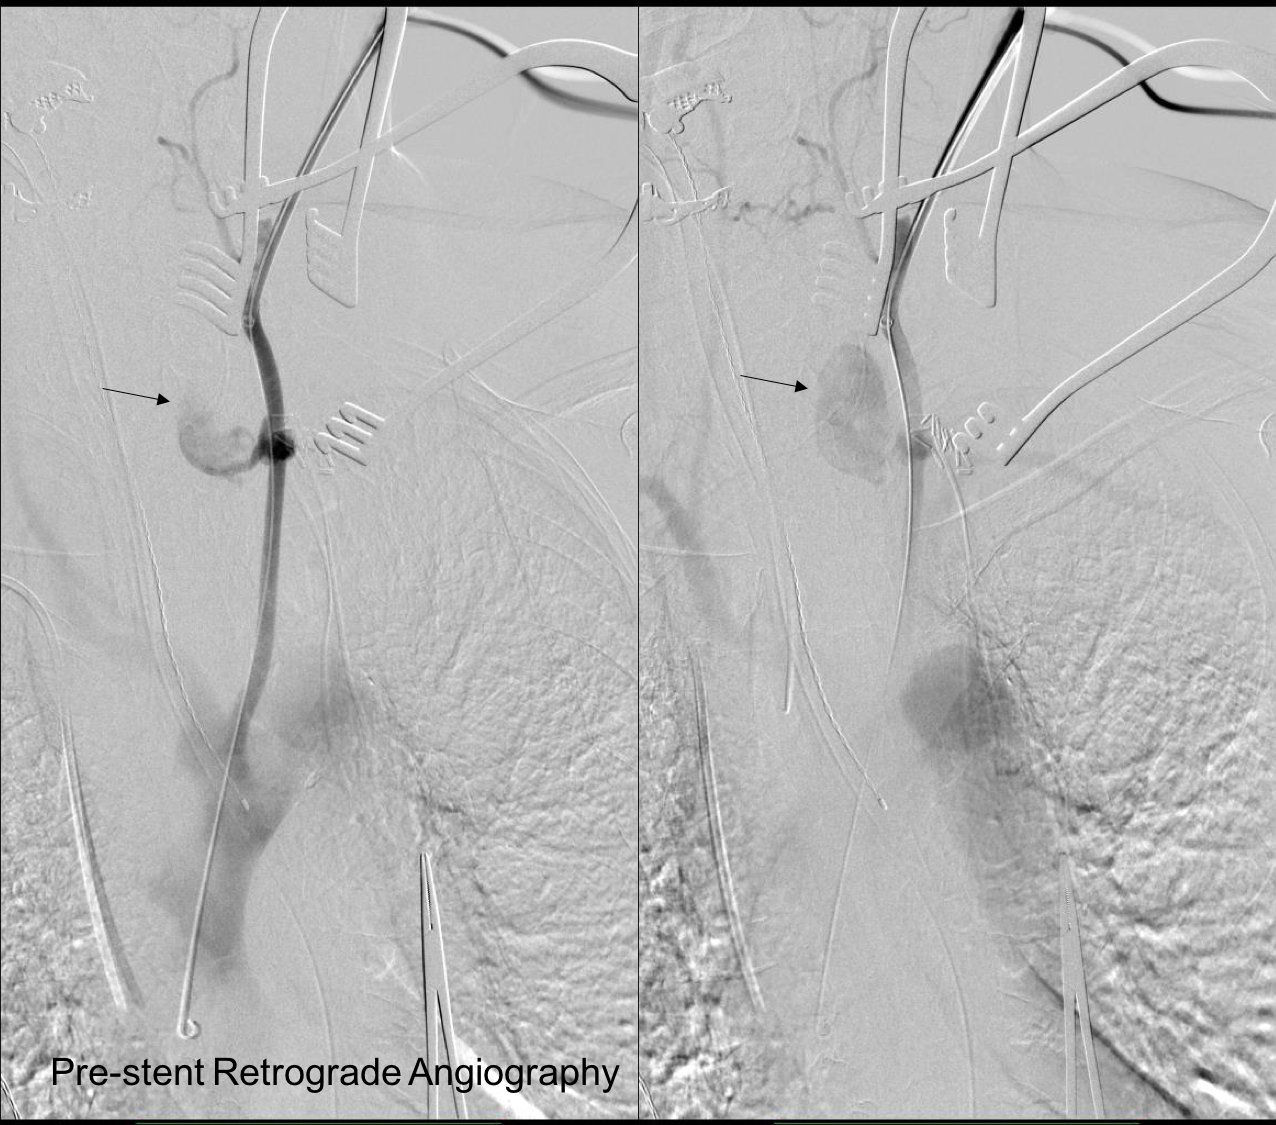

This required setting up a table off the patient’s left that allowed the wire to lie flat to be manipulated by my right hand. The carotid bifurcation was accessed through a small oblique skin line incision and the common, internal, and external carotid arteries, which were relatively atherosclerosis free, were controlled with vessel loops. The patient was heparinized. The internal carotid was occluded with the loop, and the common carotid below the bifurcation was accessed and an 8F sheath with a marker tip inserted over wire. Arteriography showed the injury and pseudoaneurysm.

prestent angiography.png

The location of the injury based on CT and on this angio would have baited a younger me into directly exposing it, but experience has taught me that which occasionally you can get away with it, the downsides -massive hemorrhage, stroke, need for sternotomy, just aren’t worth it. The sheath was brought across the injury and a Viabahn stent graft was deployed across the injury.